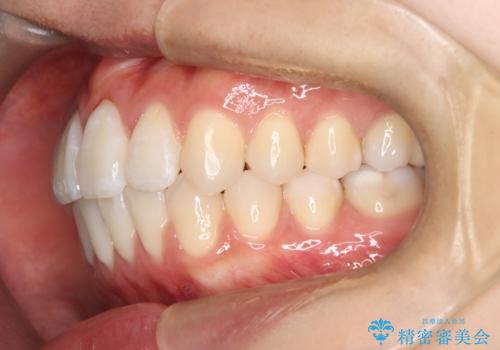

【ワイヤー矯正】前歯の突出感、下の歯の並びを良くしたい

- 主訴:上の前歯の突出感と下の歯の並びを改善したい

非抜歯で矯正治療を行った場合と、上下左右4番目の歯を抜歯して矯正治療を行った場合のシミュレーションを見ていただき、非抜歯での矯正治療を希望されました。

非抜歯にて矯正治療を行いました。

IPRを行い、前歯部の突出感の改善に努めました。

期間:1年9カ月